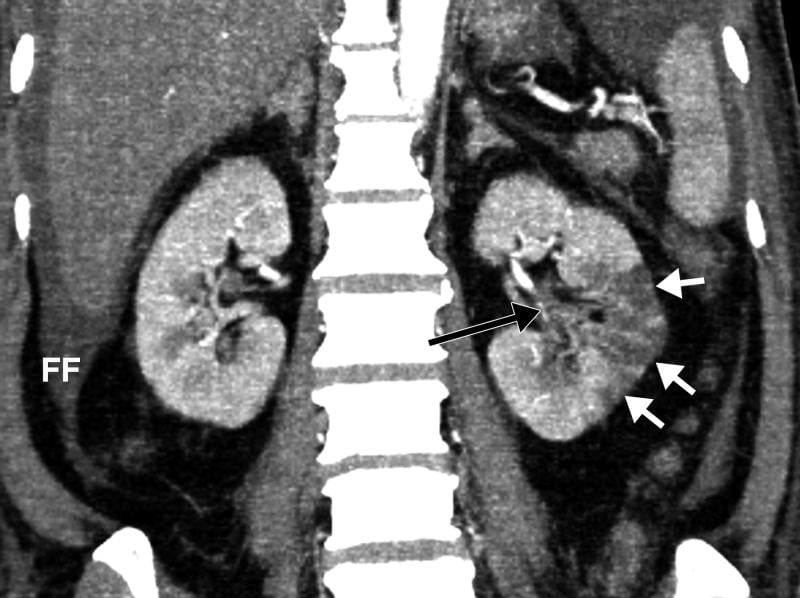

This photo gallery shows the variety of radiological presentations of COVID-19 (SARS-CoV-2) in medical imaging, including computed tomography (CT), radiograph X-rays, ultrasound, echocardiograms and magnetic resonance imaging (MRI). The radiology images show examples of typical COVID pneumonia in the lungs and the numerous complications the virus causes in the body in multiple organs, including the brain, kidneys, heart, abdomen and vascular system.

The images were collected from physicians, study authors, universities and hospitals, the National Institutes of Health (NIH), the Radiological Society of North America (RSNA), the American College of Radiology (ACR), Centers for Disease Control and Prevention (CDC) and radiology technology vendors.